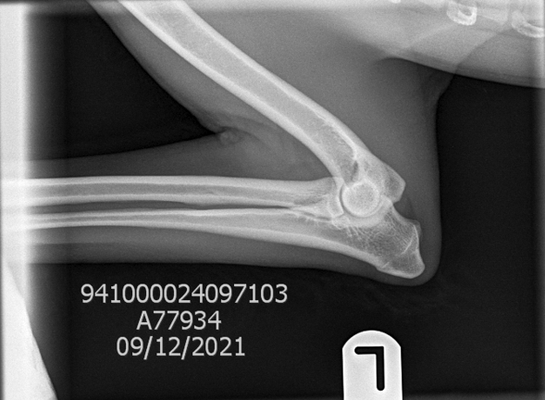

Hip & Elbow x-rays

Perhaps one of the most well known health testing in dogs, hip and elbow x-rays taken to check for signs of dysplasia. Once taken by a qualified vet the x-rays are then sent to a scoring board dependent on country of residence or personal choice of the breeder. To the right, is a comparison of the results across the most common available testing organisations.

The organisation which we primarily use for our program is BVA.

Elbows: Elbows are graded individually with a score from 0-3 on each side. The ideal being a score of 0. To have an elbow scored there must be at least two x-rays; flexed lateral and neutral view. Elbow dysplasia is uncommon in both Komondor and Mudi.

Hips: Under the BVA scheme, the marking of hips is broken down into 9 sections, the maximum marks in any one section is 6, and the maximum overall is 106. The aim is to obtain the combined lowest number possible, the best result possible being a 0. Please view the example images of our dogs results attached above to see the 9 possible sections.